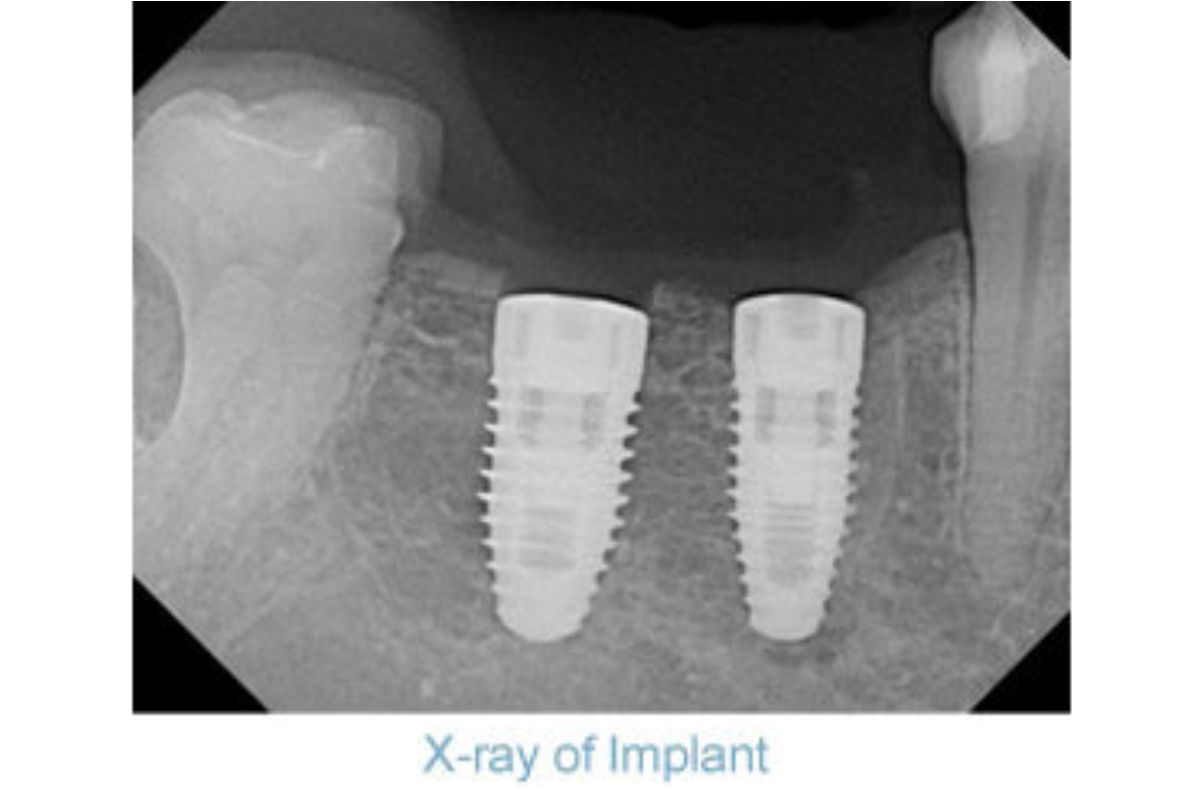

Dental implants are used as a replacement of the root of a missing tooth lost due to an accident, tooth decay or periodontal disease. They are surgical grade bio compatible titanium and integrate into the jaw where the original root of the tooth once was.

Actual patient of Dr. Sellinger